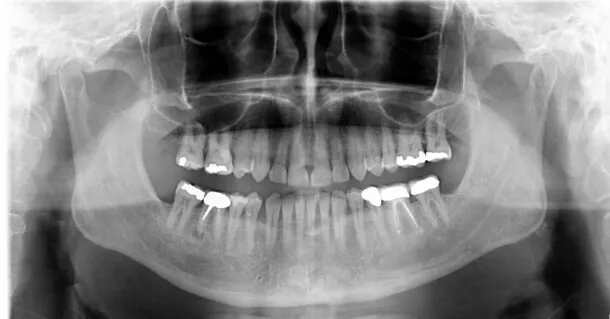

Ząb 36 to lewa dolna szóstka, czyli pierwszy ząb trzonowy dolny po lewej stronie. W systemie Viohla, który jest powszechnie stosowany w stomatologii, numer 36 oznacza ząb w dolnej lewej ćwiartce. Cyfra 6 wskazuje na jego pozycję jako szóstego zęba w tej ćwiartce. Ząb 36 jest istotnym elementem uzębienia, pełniącym kluczową rolę w procesie żucia.

Ząb 36 składa się z kilku podstawowych części, które pełnią różne funkcje. Korona zęba to widoczna część, która ma kształt przypominający płaską powierzchnię, idealną do rozdrabniania pokarmów. Korzeń zęba 36 jest głęboko osadzony w kości szczęki, co zapewnia jego stabilność. Ząb ten posiada także miąższ, w którym znajdują się naczynia krwionośne oraz nerwy, co jest kluczowe dla jego zdrowia i funkcjonowania.

Ząb 36 znajduje się w dolnej lewej ćwiartce jamy ustnej, pomiędzy zębami 35 i 37. Jest to pierwszy ząb trzonowy dolny po lewej stronie, co czyni go kluczowym elementem w układzie zębowym. Jego położenie jest istotne nie tylko dla funkcji żucia, ale także dla zachowania równowagi w całym uzębieniu. Ząb 36 pełni rolę stabilizatora, pomagając w prawidłowym ustawieniu sąsiednich zębów.

W dzisiejszych czasach nowoczesne technologie odgrywają kluczową rolę w diagnostyce i leczeniu problemów związanych z zębem 36. Wykorzystanie zdjęć rentgenowskich 3D umożliwia lekarzom dokładne zobrazowanie struktury zęba oraz otaczających tkanek, co pozwala na wczesne wykrywanie problemów, takich jak próchnica czy choroby przyzębia. Dzięki tej technologii można również precyzyjnie zaplanować leczenie, co zwiększa jego skuteczność i zmniejsza ryzyko powikłań.